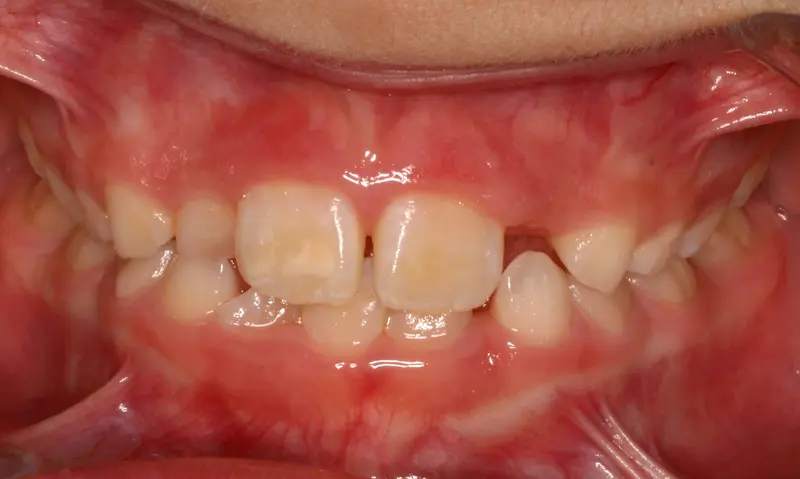

The Diagnosis

Severe crowding with blocked-out permanent teeth. The jaw size was insufficient to accommodate the erupting adult teeth, leading to significant rotation and displacement.

The Engineering

By intervening early, we utilized rapid palatal expansion to develop the arch width. This created the necessary space for the permanent teeth to erupt naturally, avoiding the need for future extractions.

Before treatment: The Expansion Phase

Before